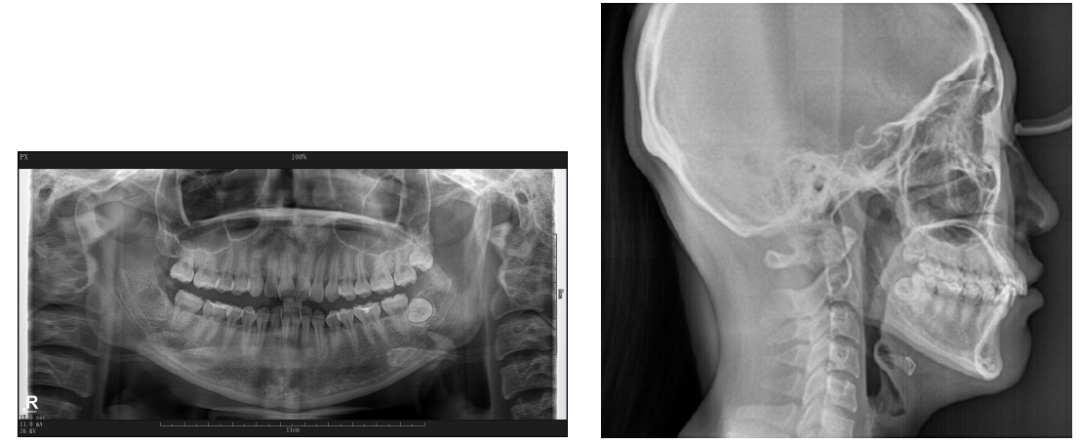

如图1-4曲断片所示:28、38阻⽣,未见牙根吸收,牙周状况良好。左侧髁突见吸收。

图1-7头影测量数据